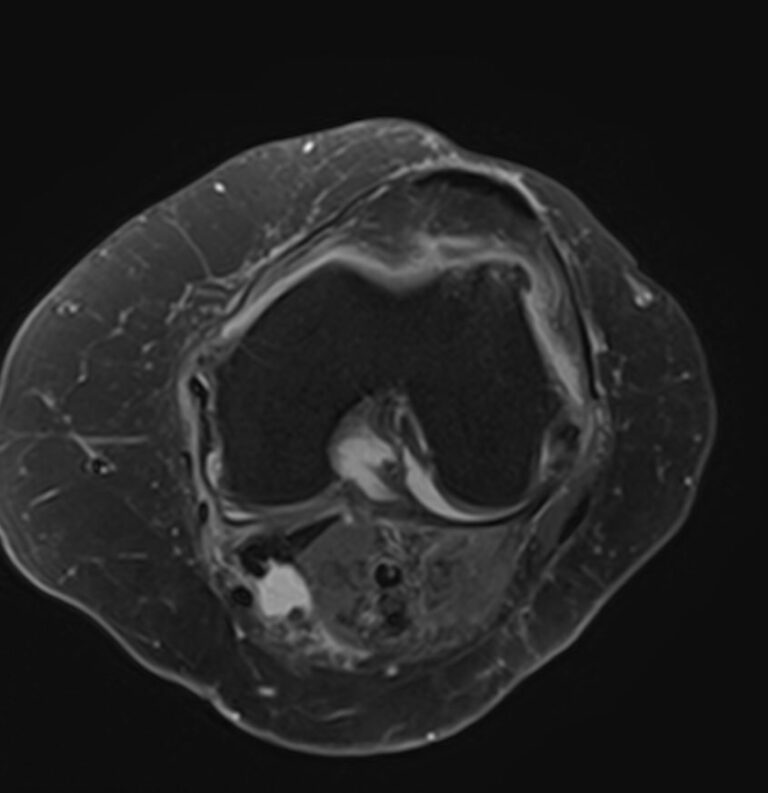

Магнитно-резонансная томография является высокоинформативным методом выявления причин возникновения заболеваний коленного сустава. В клинике «Доступная медицина» диагностика осуществляется на новейшем высокопольном томографе закрытого типа TOSHIBA VANTAGE TITAN 1,5 Тесла, обеспечивающем высочайшее качество изображений исследуемой зоны.

Томограф позволяет детально визуализировать как костные структуры колена, так и окружающие мягкие ткани данной анатомической области, включая мышцы, связки, нервные сплетение, сосуды.